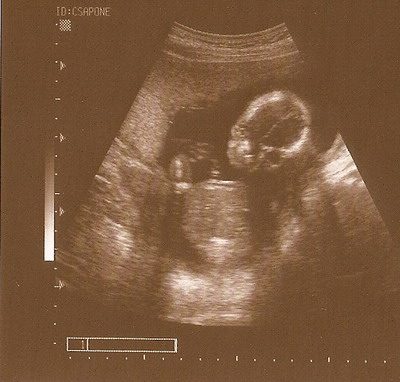

Ercsi nagyon édes Csipetke :D Néztem a méreteit, kicsit nagyobb mint Mazsi, de szerintem ez azért van mert 4 nappal később voltatok :wink: Ezek szerint gyakorlatilag hajszálra egyidősek :D

Ercsi - Cukik a képek :)

Nem olyan régen láttam ugyan .. de az utolsó kötelező Uh meg sem közelítette a 16 hetes 4D-t .. :roll: :roll: Az meg már nagyon nagyon régen volt ... :roll: